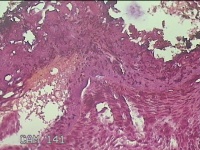

外阴赘生物

性别

女

年龄

33岁

临床诊断

外阴尖锐湿疣

一般病史

发现外阴尖锐湿疣4个月。

标本名称

大体所见

灰白暗红色不规则碎组织0.3x0.2x0.1cm一堆。

图2

良性病变,考虑湿疣。